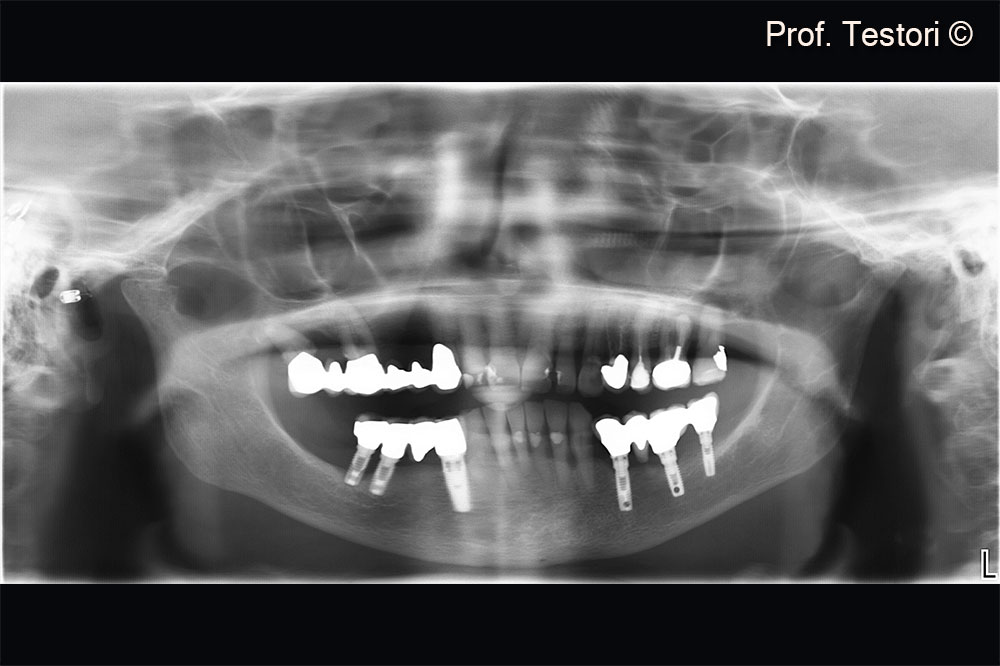

Radiographic evaluation at consultation visit.